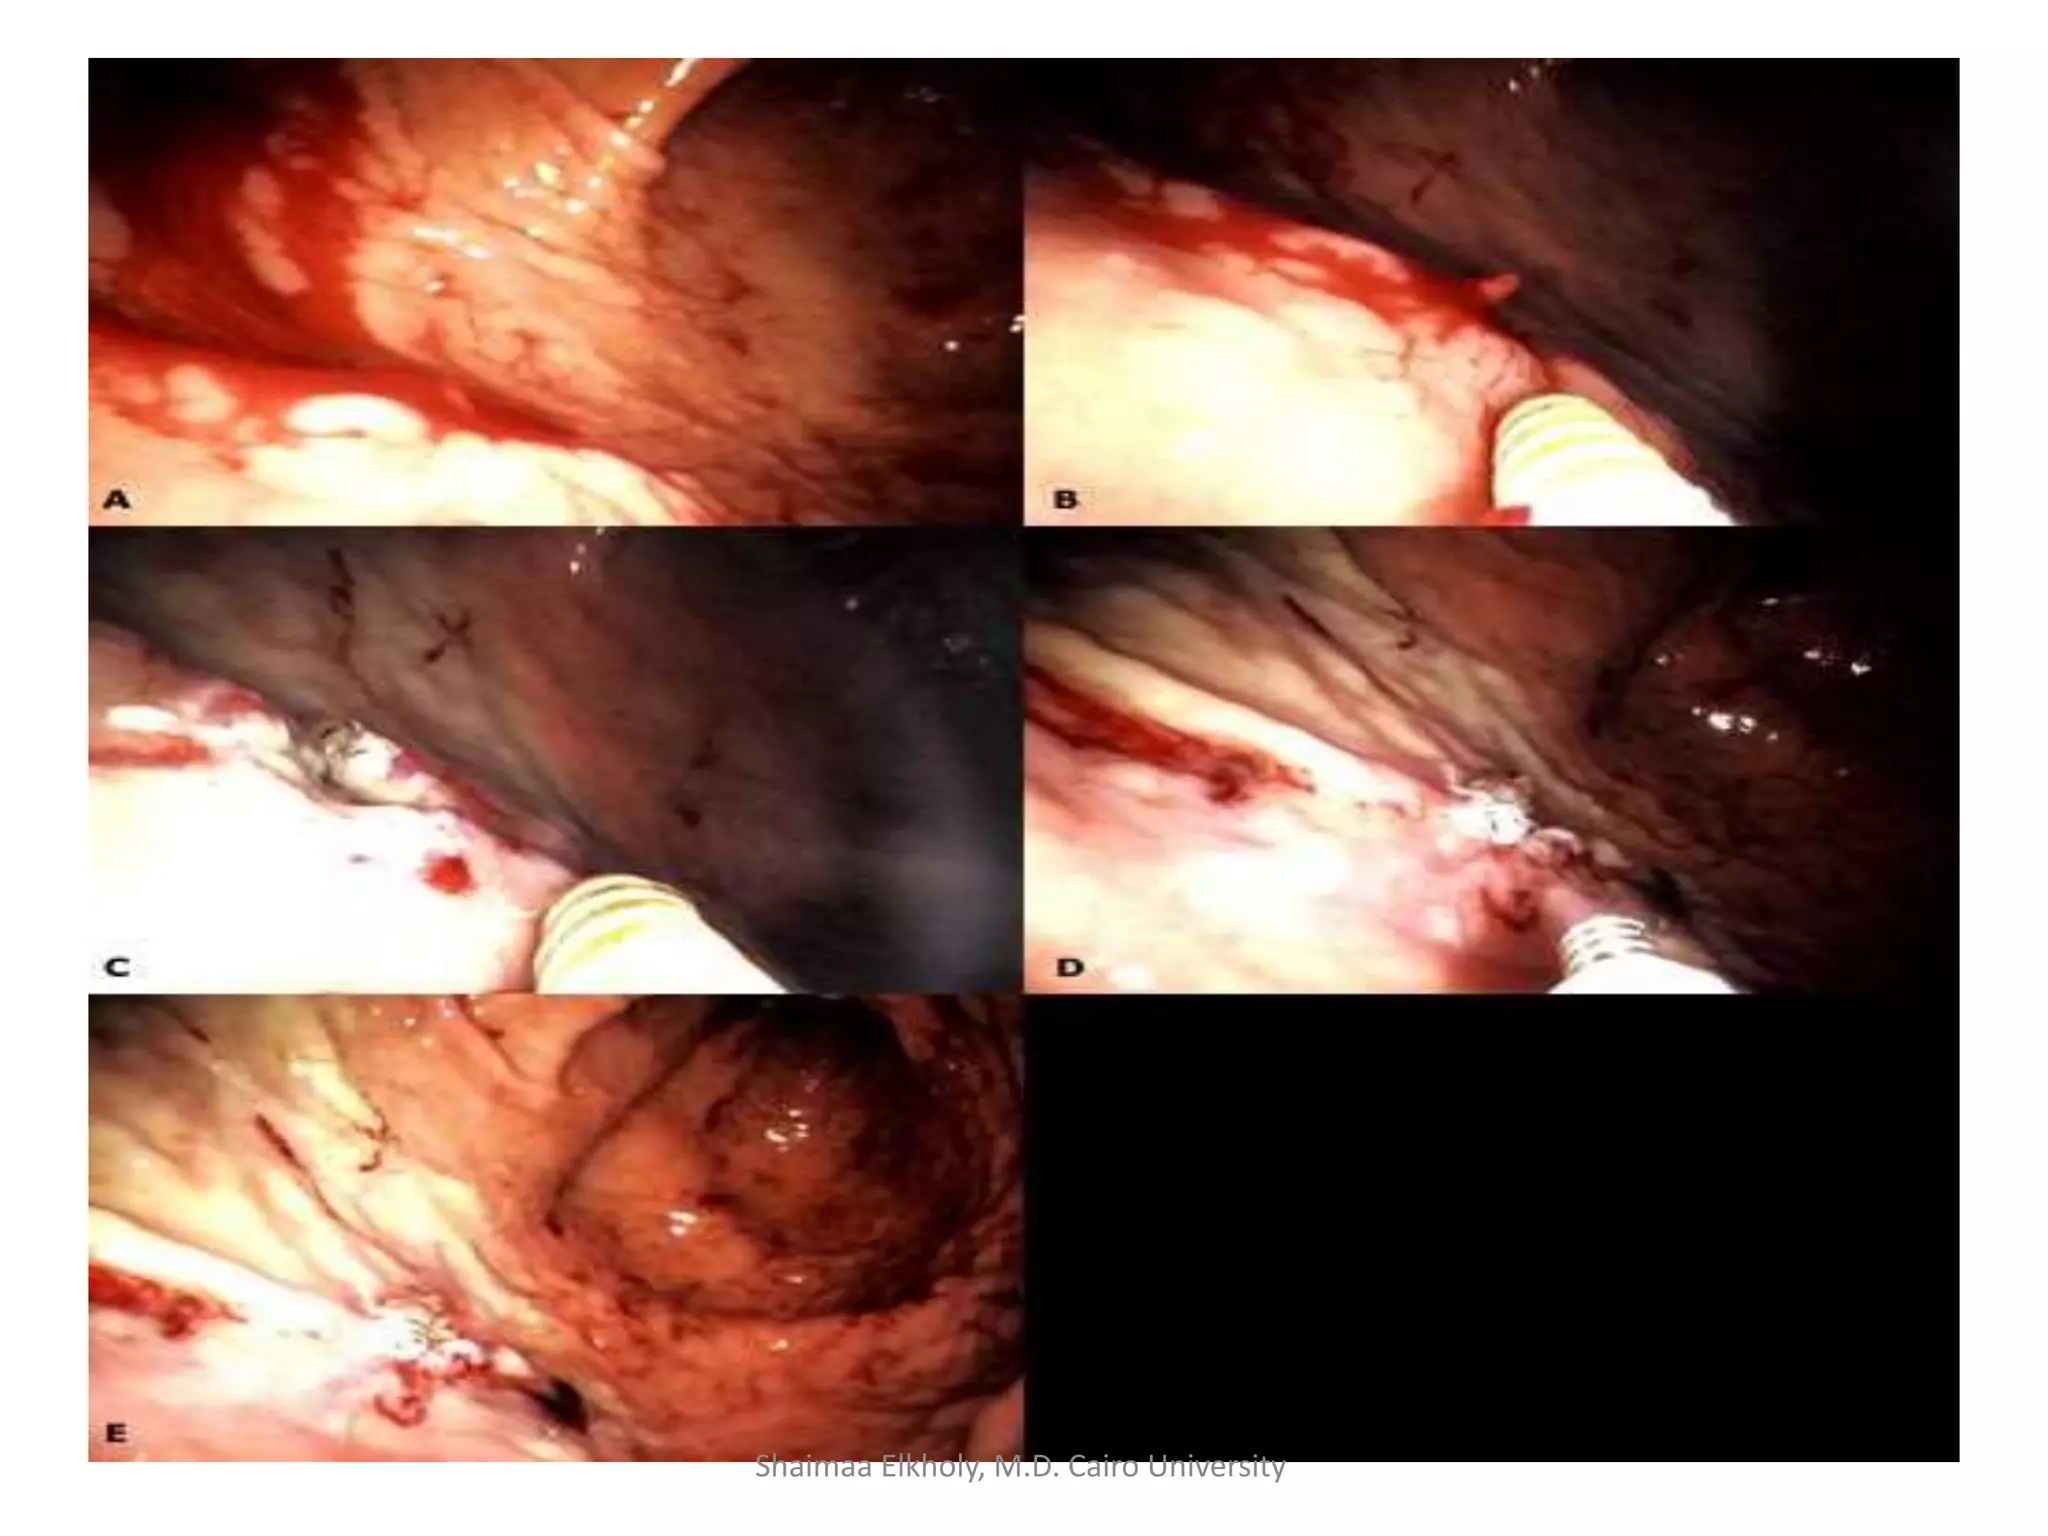

Endoscopic management VUGIB:

Video 1

Video 2

Video 3

Shaimaa Elkholy, M.D. Cairo University

• EVL:

endoscopic

variceal

ligation

• Less

complications

e.g. ulcers,

stricture

(rare).

• Less sessions.